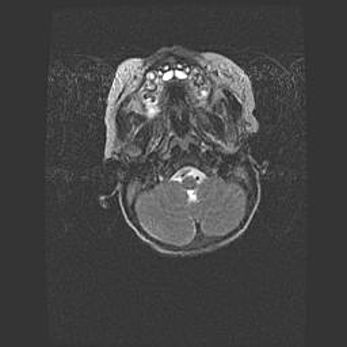

Подострая гематома правой гемисферы мозжечка.

Наружная гидроцефалия.

Возраст: 15 дней

Вес: 3100 г

Пол: женский

Окружность головы: 37 см

Срок гестации: 35-36 недель

При открытой наружной форме гидроцефалии у новорожденных расширяются и переполняются субарахноидные пространства.

Кровоизлияния в мозжечок имеют две клинико-анатомические формы: полушарные гематомы и кровоизлияния в червь.

К появлению этой патологии может привести: повреждения головного мозга, возникающие в результате асфиксии и гипоксии плода при беременности, или травмы во время родов. Редко гематома мозжечка может быть результатом первичной коагулопатии и сосудистой мальформации, диссеминированном внутрисосудистом свертывании, изоиммунной тромбоцитопении.